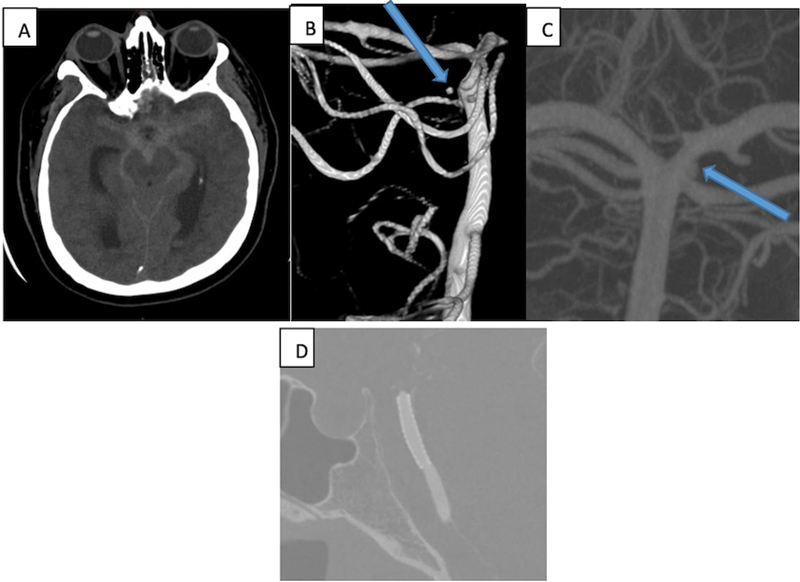

Objectives Subarachnoid hemorrhage (SAH) resulting from rupture of basilar artery perforator aneurysm (BAPA) is a neurological rarity. With increased awareness and advancements in imaging modalities, they are now more frequently detected. However, concerns regarding their suboptimal treatment and lack of proper analysis still exist. We are hereby reporting our experience of treating this entity in a small cohort. Materials and Methods  It is a retrospective study of all the cases of SAH resulting from rupture of BAPA, which were treated by the same surgical team. Demographic data, treatment characteristics, and follow-up data of our cases along with published literature were studied. Results  Our cohort comprised of five patients (mean age 55 years). Three cases were treated with flow diverter alone and the rest underwent flow diverter and overlapping stent placement. Initial diagnostic cerebral angiography (digital subtraction angiography) was negative in three of them. There was one mortality and favorable outcome was encountered in the remaining cases. All of them demonstrated complete occlusion of the aneurysm in follow-up. Conclusion  Following treatment, all the cases demonstrated complete angiographic occlusion of the aneurysm. In available literature, studies have small sample sizes. Future randomized studies in a larger cohort and proper reporting and analysis of outcomes will help us formulating a treatment protocol for BAPA.

Abstract Image